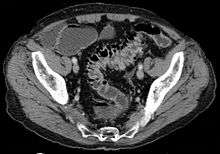

In cases of asymptomatic diverticulosis, the diagnosis is usually made as an incidental finding on other investigations.

- Contrast CT is the investigation of choice in acute episodes of diverticulitis and where complications exist.